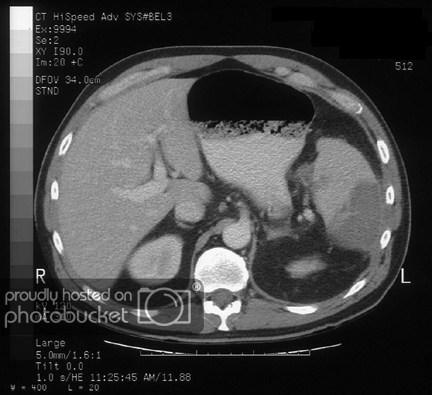

Click vào ảnh để xem 5 hình ảnh minh họa